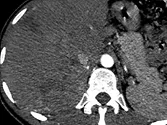

Figure 7. Carcinome hépatocellulaire traité par sorafénib.

Sur l’examen initial (A), la lésion présente deux compartiments sur cette image d’IRM au temps artériel l’un nécrotique, l’autre qui se rehausse, appelé tumeur « viable ».

B. Mesure selon mRECIST du plus grand diamètre de la lésion viable.

C et D. Après quatre mois de chimiothérapie, le compartiment viable de la tumeur passe de 37 à 24 mm, soit une diminution de 35 %. Il s’agit donc d’une réponse partielle, alors que le volume total de la lésion n’a pas changé.

Selon RECIST 1,1, la réponse aurait été « SD »